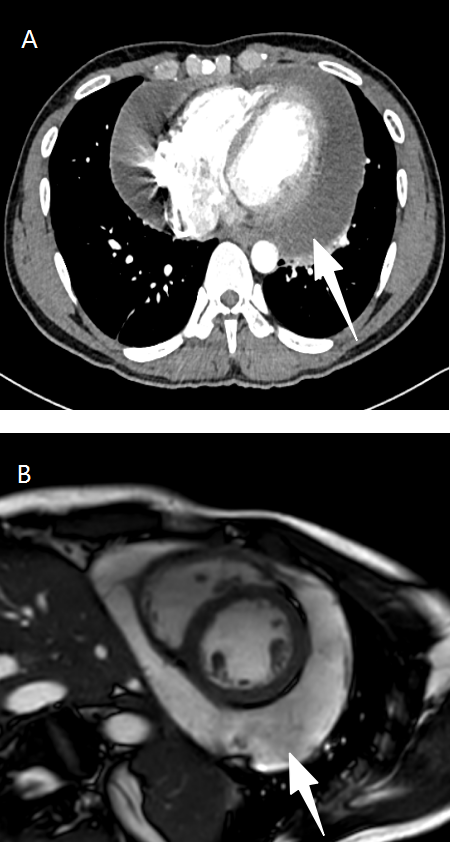

This article reports the diagnosis and treatment process of one case of sparganosis mansoni. The patient was a young man, admitted to the hospital due to “substernal pain accompanied by shortness of breath for over a week”. Cardiac MR and enhanced chest CT examinations revealed large amount of pericardial effusion. Hemorrhagic exudate was found by pericardiocentesis, and routine laboratory examination of the pericardial effusion showed a significant increase in the proportion of lymphocytes and adenosine deaminase (ADA) levels. He was initially suspected to be tuberculosis infection, yet no evidence could support this conclusion by additional laboratory studies, including mNGS of the pericardial effusion, T-SPOT.TB, and sputum AFB smear. Further inquiry into the medical history revealed that the patient had a history of consuming raw frog meat. Both routine blood test and biochemical analysis of the pericardial effusion indicated elevated eosinophils, and the serum antibody test positive for Spirometra mansoni. Consequently, empirical therapy with praziquantel was initiated. After medication, the patient’s clinical symptoms were significantly improved, and follow-up examination showed resolution of the pericardial effusion. The patient was ultimately diagnosed with an infection caused by sparganosis mansoni.